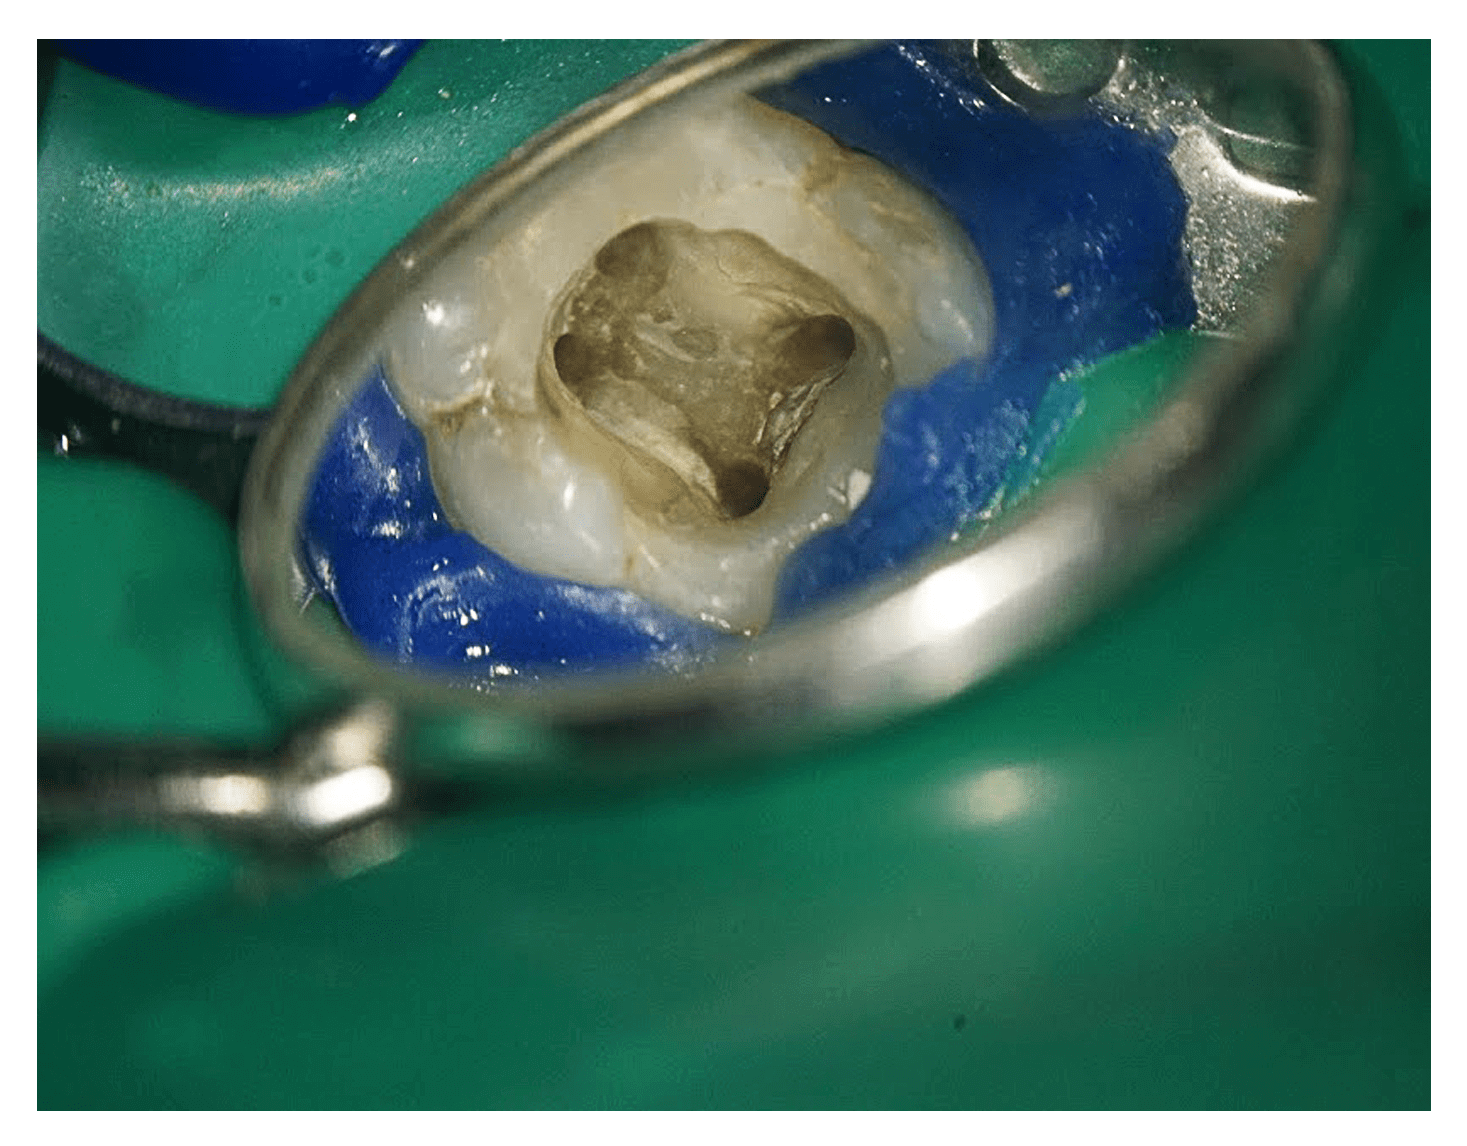

A hagyományos gyökérkezelés remekül működik a frontfogaknál és a szemfogaknál. Az őrlőfogak azonban már egy szinttel feljebb vannak, már ami a nehézségeket illeti. Az előbb említett fogaknál ugyanis a foggyökerek és a bennük futó foggyökércsatornák szabad szemmel is jól felderíthetők, kezelhetők. Az őrlőfogaknál azonban már a gyökércsatornákat sem oly egyszerű megtalálni – ne feledjük, hogy a foggyökércsatornák az íny alatti részben vannak!

A foggyökerekben futó foggyökércsatornák nagyon bonyolult hálózatot alkothatnak. A begyulladt, fájdalmat okozó szakasz maradéktalan felderítése, kitisztítása szabad szemmel gyakorlatilag lehetetlen. Ha szerencsés a páciens, megeshet, hogy a „vak tyúk is talál szemet” elve érvényesül, és pont a gyulladt részt találja meg a szabad szemmel dolgozó fogorvos – ám ennél gyakoribb, hogy a sikeresnek hitt gyökérkezelés után csak nem múlik a sajgás.

A mikroszkóppal dolgozó szakember viszont alaposan, szakaszról szakaszra végigpásztázza a foggyökércsatornákat, és így minden gyulladásban levő vagy elhalt szövetet meg tud találni és el tud távolítani.